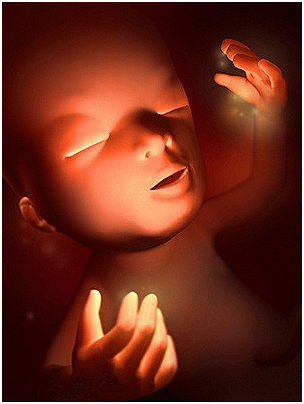

怀孕第38周恭喜准妈妈,从现开始你的宝宝已经是足月儿了,随时可能出来和你见面哦!你现在是不是...

怀孕第38周恭喜准妈妈,从现开始你的宝宝已经是足月儿了,随时可能出来和你见面哦!你现在是不是... -